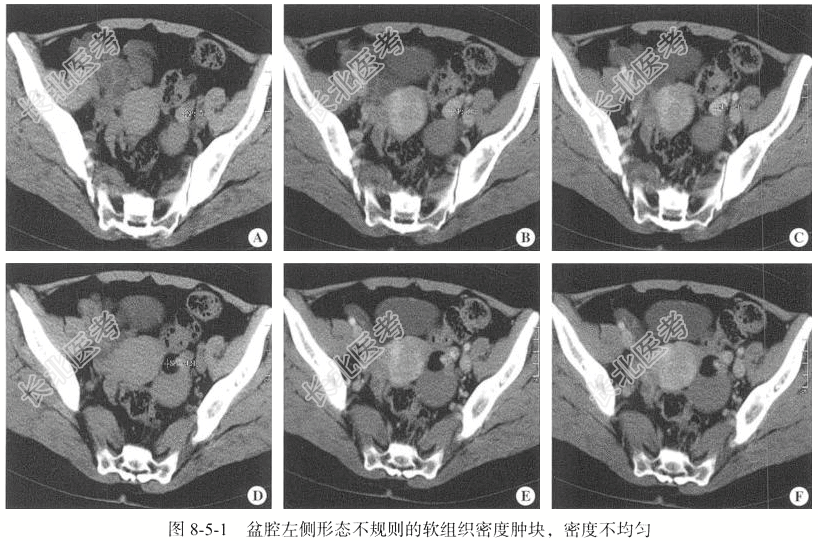

- [材料题] 【临床病史】女性,42岁。盆腔无痛性包块7年。

【专科查体】宫体:前位,如孕9周大小,质硬,表面凹凸不平,形态欠规整,活动可,无压痛;双侧附件:左侧附件区触及大小约6cm包块,边界清,表面光滑,活动可,无压痛;右侧未触及明显肿块。

【影像图片】见图8-5-1。

【手术所见】子宫前位,如孕9周大小,子宫后壁饱满,左侧卵巢囊性增大,大小约7cm×6cm×6cm,与同侧盆壁及部分肠管、网膜粘连,双侧输卵管及右侧卵巢外观正常。用穿刺吸引器刺入囊肿,见咖啡色囊液流出,吸净囊液,剥除囊壁,见囊肿为多房状,囊腔内另见子囊,子囊液呈稀薄淡黄色油脂样。

【病理所见】(左侧卵巢囊肿)囊壁样组织一堆,大小为2.5cm×2cm×0.8cm,壁厚0.1~0.2cm,内外壁光滑,呈淡粉色,质韧。(左侧卵巢囊肿底部)不整组织一块,大小为1.4cm×1cm×0.8cm,似有包膜(图8-5-2),表面呈灰红色,切面呈灰黄色,质中。

【病理诊断】(左侧卵巢囊肿底部)卵巢甲状腺肿。